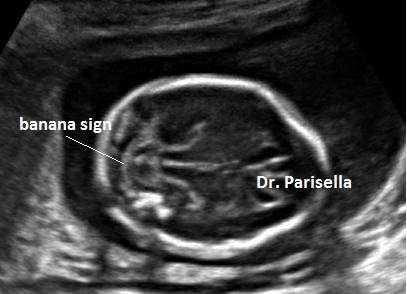

2) cervelletto a banana;

I primi tre segni (segno del limone, obliterazione della cisterna magna, cervelletto a banana), c.d. segni indiretti, hanno una elevata sensibilità nella diagnosi dei difetti aperti e sono espressione della sindrome di Chiari tipo 2. Questa è la conseguenza della perdita di liquido cefalo-rachidiano attraverso il difetto spinale; la diminuzione della pressione idrostatica provoca iposviluppo della fossa cranica posteriore con conseguente erniazione del tronco encefalico e del cervelletto che si piega assumendo il classico aspetto a banana. La perdita di liquido cerebrospinale attraverso il difetto spinale provoca un aumento dei livelli di alfa-fetoproteina nel liquido amniotico e nel siero materno.